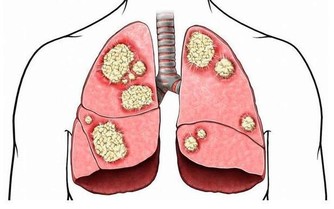

3、抗結核藥物

吡嗪酰胺和乙胺丁醇是熟知的抗結核藥,你如果看看藥物的使用說明書,裡面清楚的寫著,可能會導致尿酸增高。但是,很有意思的是,同樣作為抗結核藥物的利福平卻可以抑制尿酸的吸收,如果將這三種抗結核物質一起服用,並不會引起尿酸的過度升高。

5、抗腫瘤的藥物

環磷酰胺是非常常見的抗腫瘤藥物,它也能夠升高尿酸,容易產生高尿酸血症。